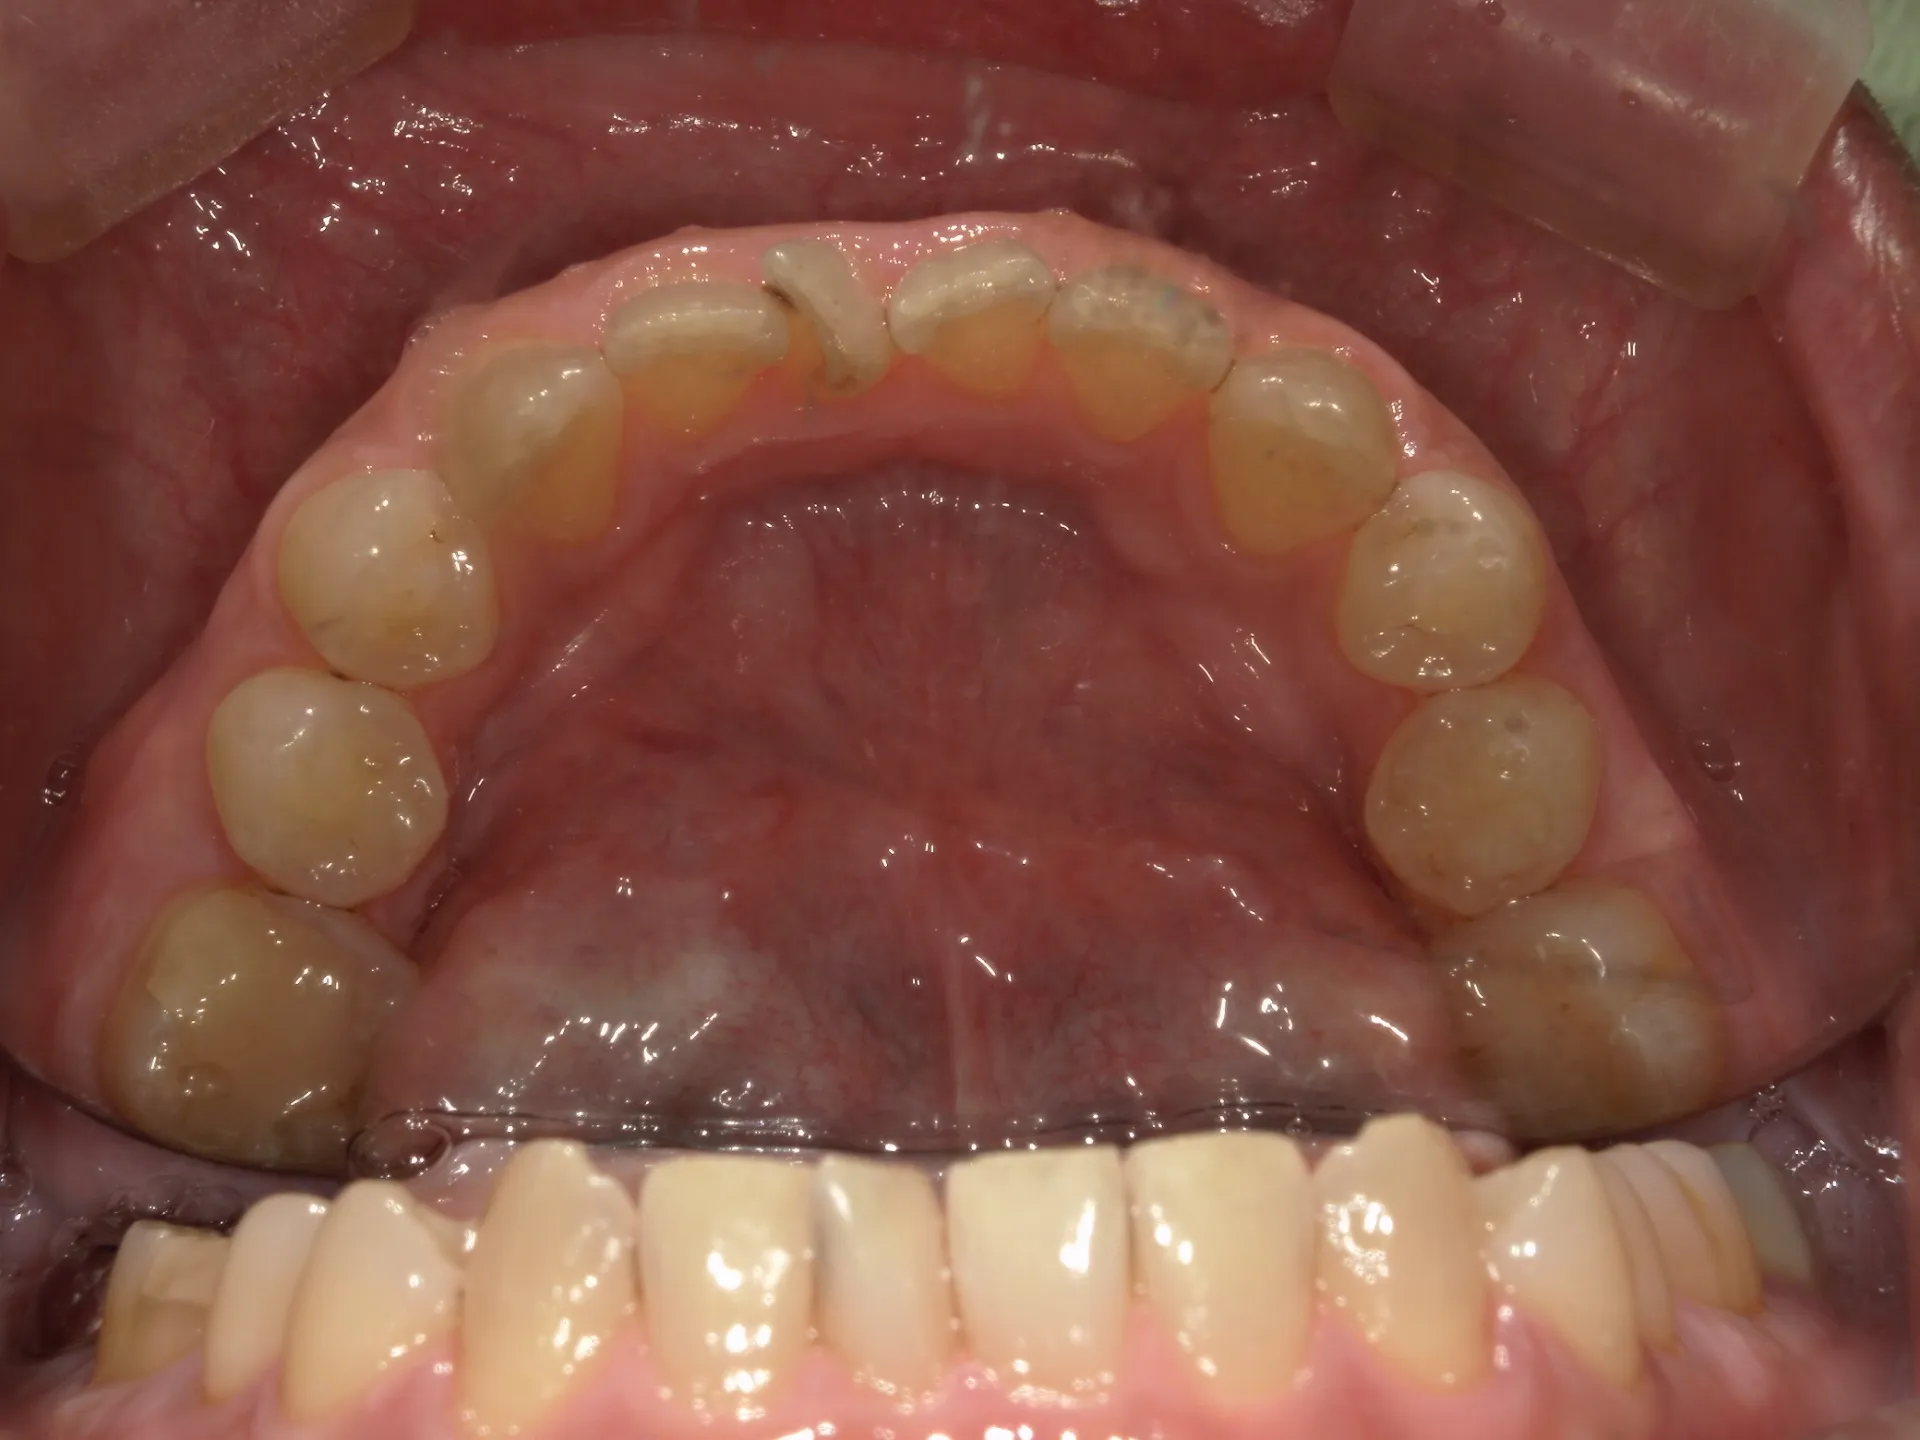

① 保険の歯の掃除(スケーリング・ルートプレーニングなど)

目的:歯周病(歯肉炎・歯周炎)の治療、進行予防

対象:歯石やプラークの除去

範囲:医療行為として認められた範囲のみ(歯石やプラークがついていないと保険は算定できません)

内容:歯周ポケット検査を行い、その後超音波スケーラーや手用スケーラーで歯肉縁上・縁下の歯石を取る